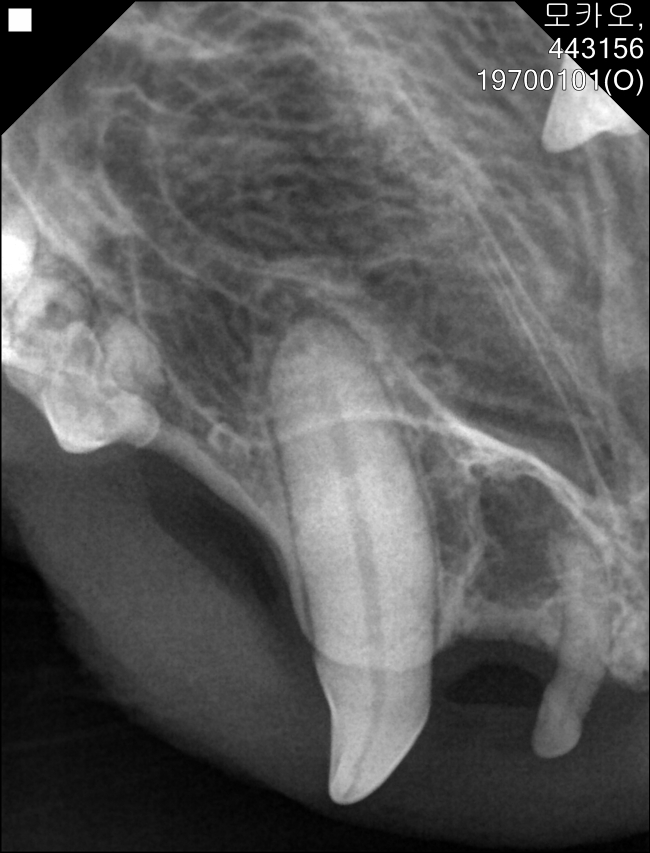

치료전 대상묘

2020년 중성화수술당시 모카오

모카오구조 2022년11월

구조후 상태 |

치료중 대상묘